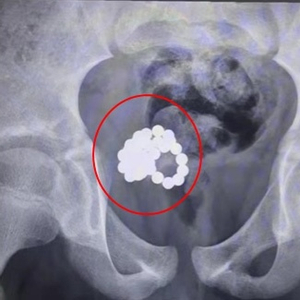

当医生们还在为这个孩子唏嘘不已的时候,门诊又来了一个同为11岁的男孩。这个男孩如实地讲出了他往尿道里放东西的情况,影像检查显示,孩子的膀胱内有数十颗金属磁力珠吸引在一起。

医生从11岁男童体内取出的磁力珠。上海交大医学院附属新华医院 供图

与前一例情况相似,为了减少手术创伤,医生们尝试了各种微创手段,但却因磁力紧紧吸引,无法成功操作。最终医生只能选择传统手术方式,取出了34颗磁力珠。